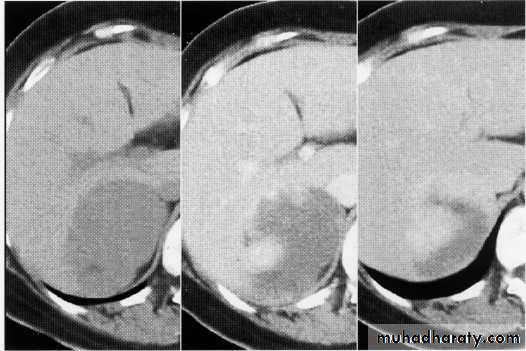

hemangeoma